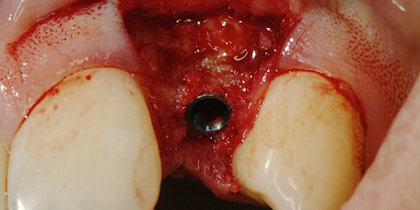

• A Glidewell HT is immediately placed into the extraction socket of a maxillary central incisor. thumbnail image

Extraction with Immediate Placement

A Glidewell HT is immediately placed into the extraction socket of a maxillary central incisor.

• A Glidewell HT Implant is immediately placed following the extraction of tooth #19. thumbnail image

A Glidewell HT Implant is immediately placed following the extraction of tooth #19.

• Tooth #30 is extracted and immediately replaced with a Glidewell HT Implant. thumbnail image

Tooth #30 is extracted and immediately replaced with a Glidewell HT Implant.